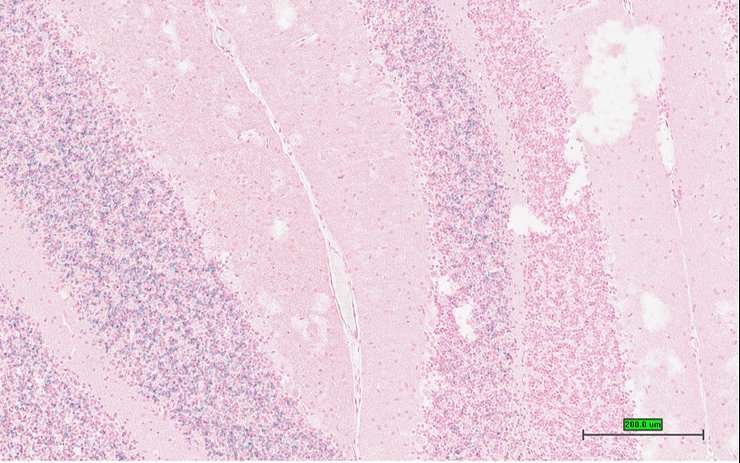

TS28: cerebellum Present UC Davis_1851941

Specimen UC Davis_1851942: postnatal adult; Syndig1ltm1.1(KOMP)Vlcg/Syndig1l+ (more )

Structure Level Pattern Image Note

TS28: cerebellum Present UC Davis_1851942

Specimen UC Davis_1851943: postnatal adult; Syndig1ltm1.1(KOMP)Vlcg/Syndig1l+ (more )

TS28: cerebellum Present UC Davis_1851943